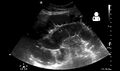

Small bowel obstruction on ultrasound[19]